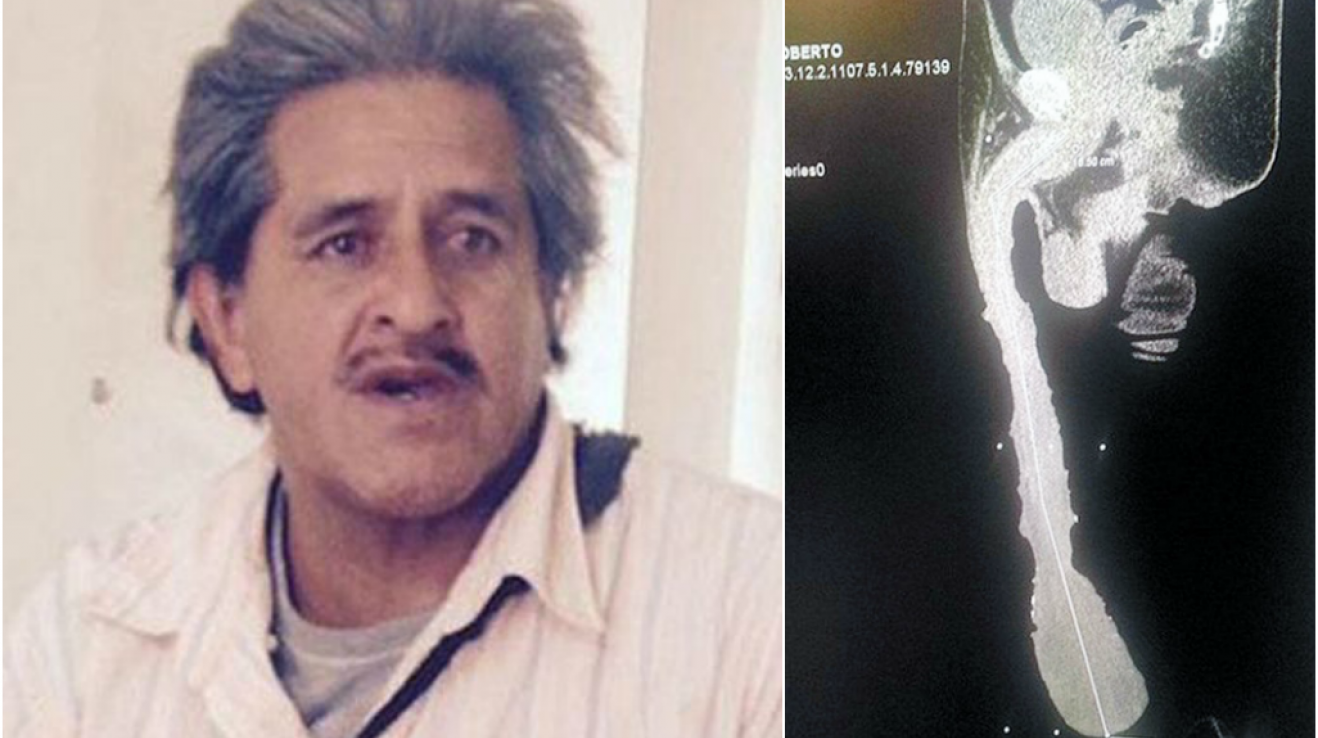

Pan Cabrera nedávno podstoupil speciální lékařskou prohlídku, v jejímž rámci mu byl penis spolu s příslušenstvím zrentgenován ve 3D. Doktoři potvrdili, že se jedná o zcela přirozený úkaz. A Cabrera teď snímek ukazuje všem, kdo by o jeho světově rekordním penisu chtěli mít nějaké pochyby.

Ačkoli, jak lékaři po řádném prozkoumání rentgenových snímků dodávají: „Tělo penisu má ve skutečnosti na délku něco přes průměrných patnáct centimetrů, zbytek tvoří kůže, byť v nevídaně nadměrném množství.“